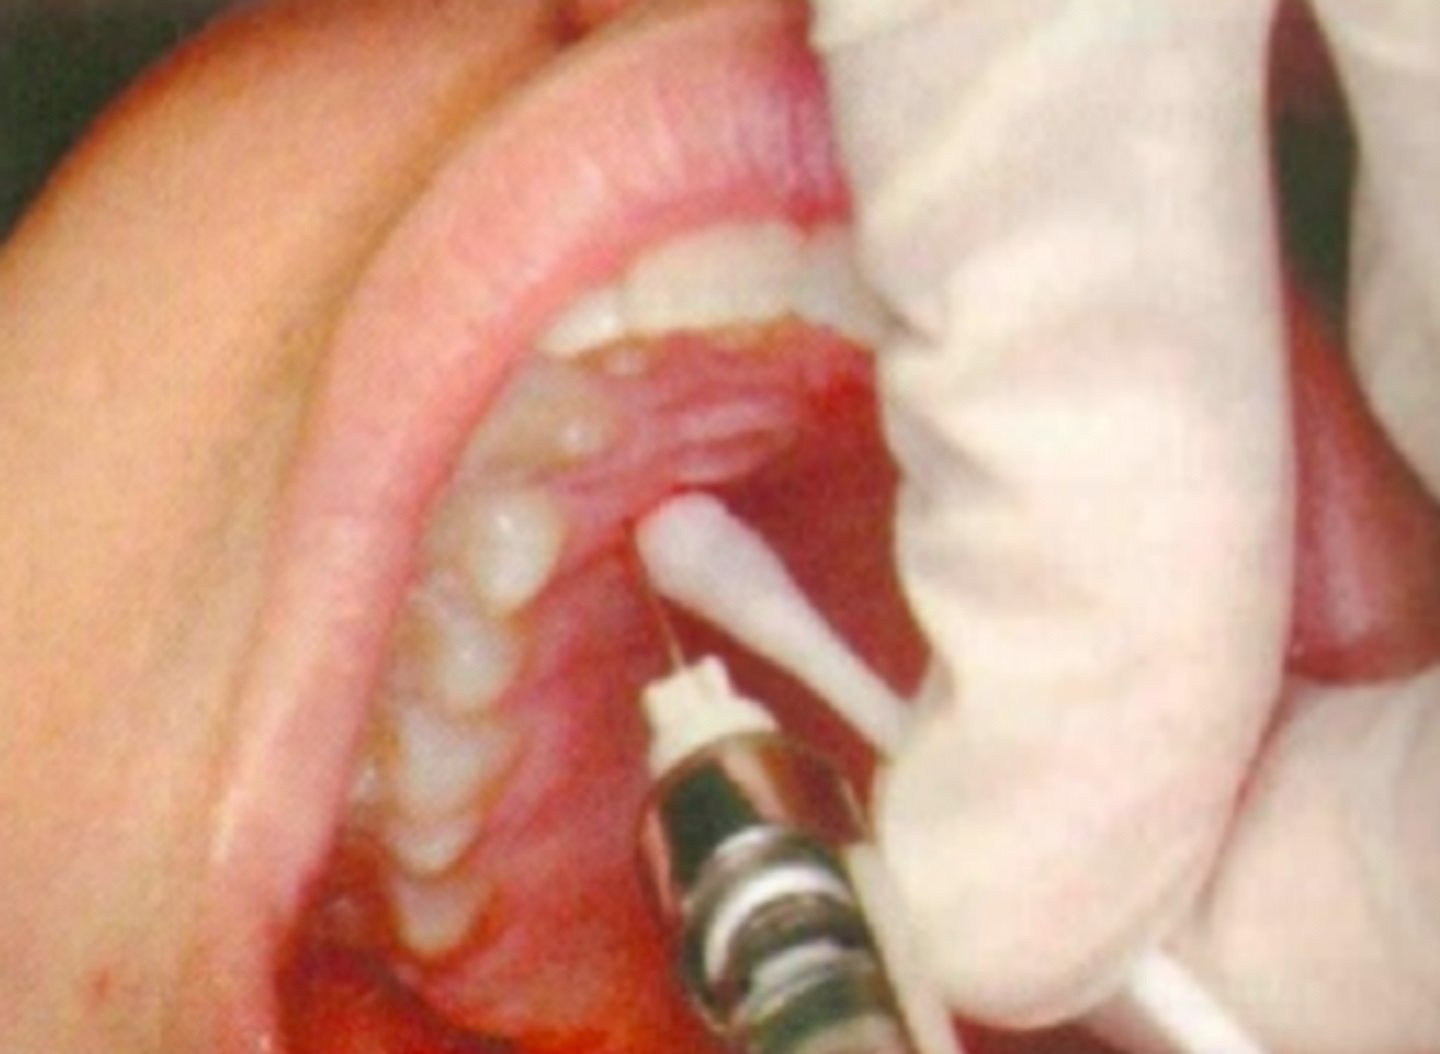

Palatogingival pain control for limited area (1-2 teeth) Achieving hemostasis during surgical procedure

What are the indications for a Palatal local infiltration?

-Infection/inflammation at injection site

-Smaller area of therapy (1 or 2 teeth)

What are some contraindications for a Palatal local infiltration?

Palatal Local Infiltration

ID the anesthesia technique:

27 short gauge

what size needle should you use for a Palatal Local Infiltration?

Palatal gingival tissue 5-10 mm from the free gingival margin

what is the needle target for a Palatal Local Infiltration?

Attached gingiva 5-10 mm from the free gingival margin

what is the insertion point for a Palatal Local Infiltration?

Approaching the injection site at 45 degree angle

what is the insertion path for a Palatal Local Infiltration?

3 to 5 mm

what is the insertion depth for a Palatal Local Infiltration?

0.2 to 0.3 ml

what is the anesthetic volume for a Palatal Local Infiltration?

This type of nerve block will result in the anesthesia of the palatal soft tissue in the immediate adjacent area of injection?